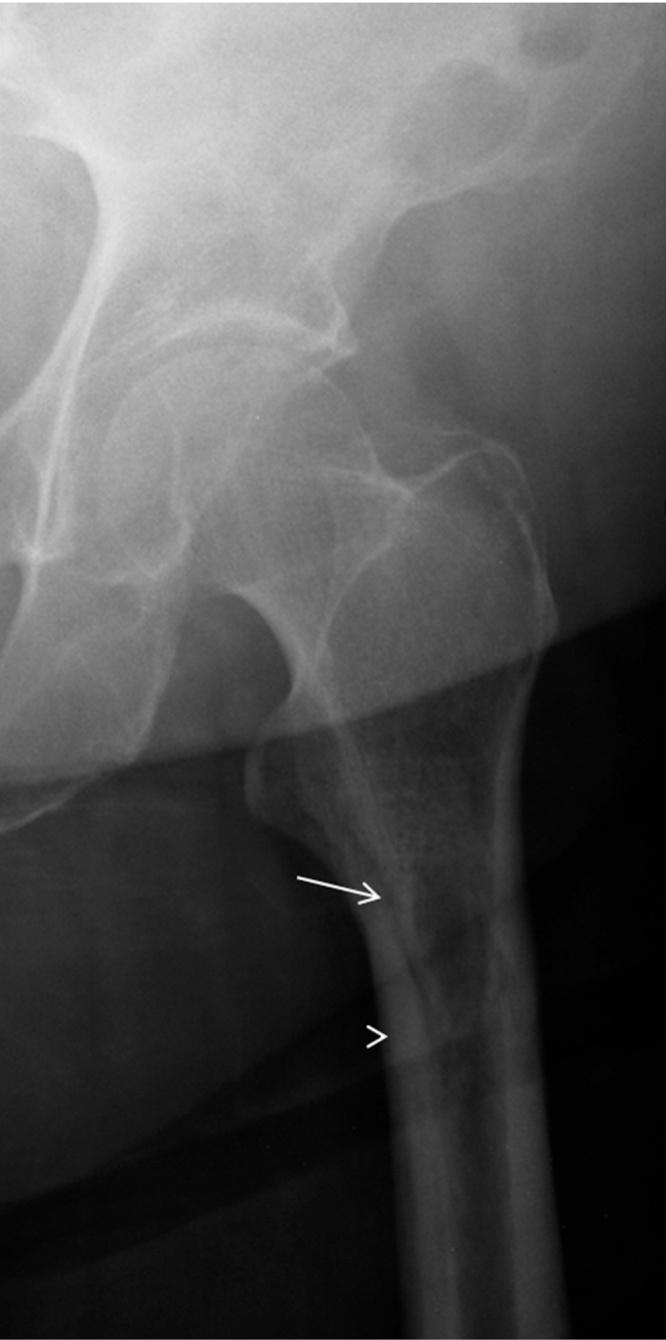

股骨纵向应力性骨折:一种罕见的表现。

Longitudinal stress fracture of the femur: A rare presentation.

We present the case of an 80 year old woman with hip pain, caused by a longitudinal femoral insufficiency stress fracture, depicted with radiographs, CT and MR. This type of fracture is very rare, with only a few cases reported. We conducted a literature review and compared the findings with the present case.

摘要

我们报告一例80岁女性因股骨纵向应力性骨折导致髋部疼痛的病例,通过X线片、CT和磁共振成像(MR)进行了描述。这种类型的骨折非常罕见,仅有少数病例报道。我们进行了文献综述,并将研究结果与本病例进行了比较。